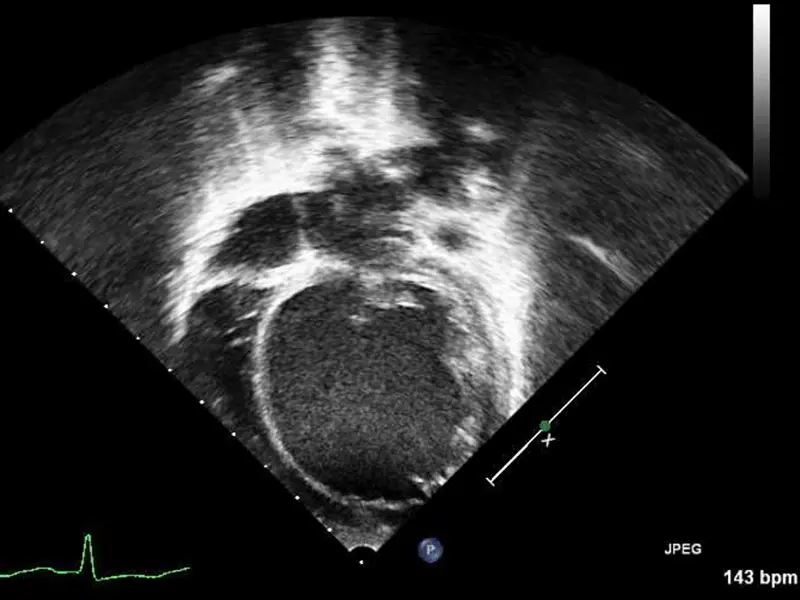

Echocardiogram showing severely dilated left ventricle on arrival to Mount Sinai Kravis Children’s Hospital.